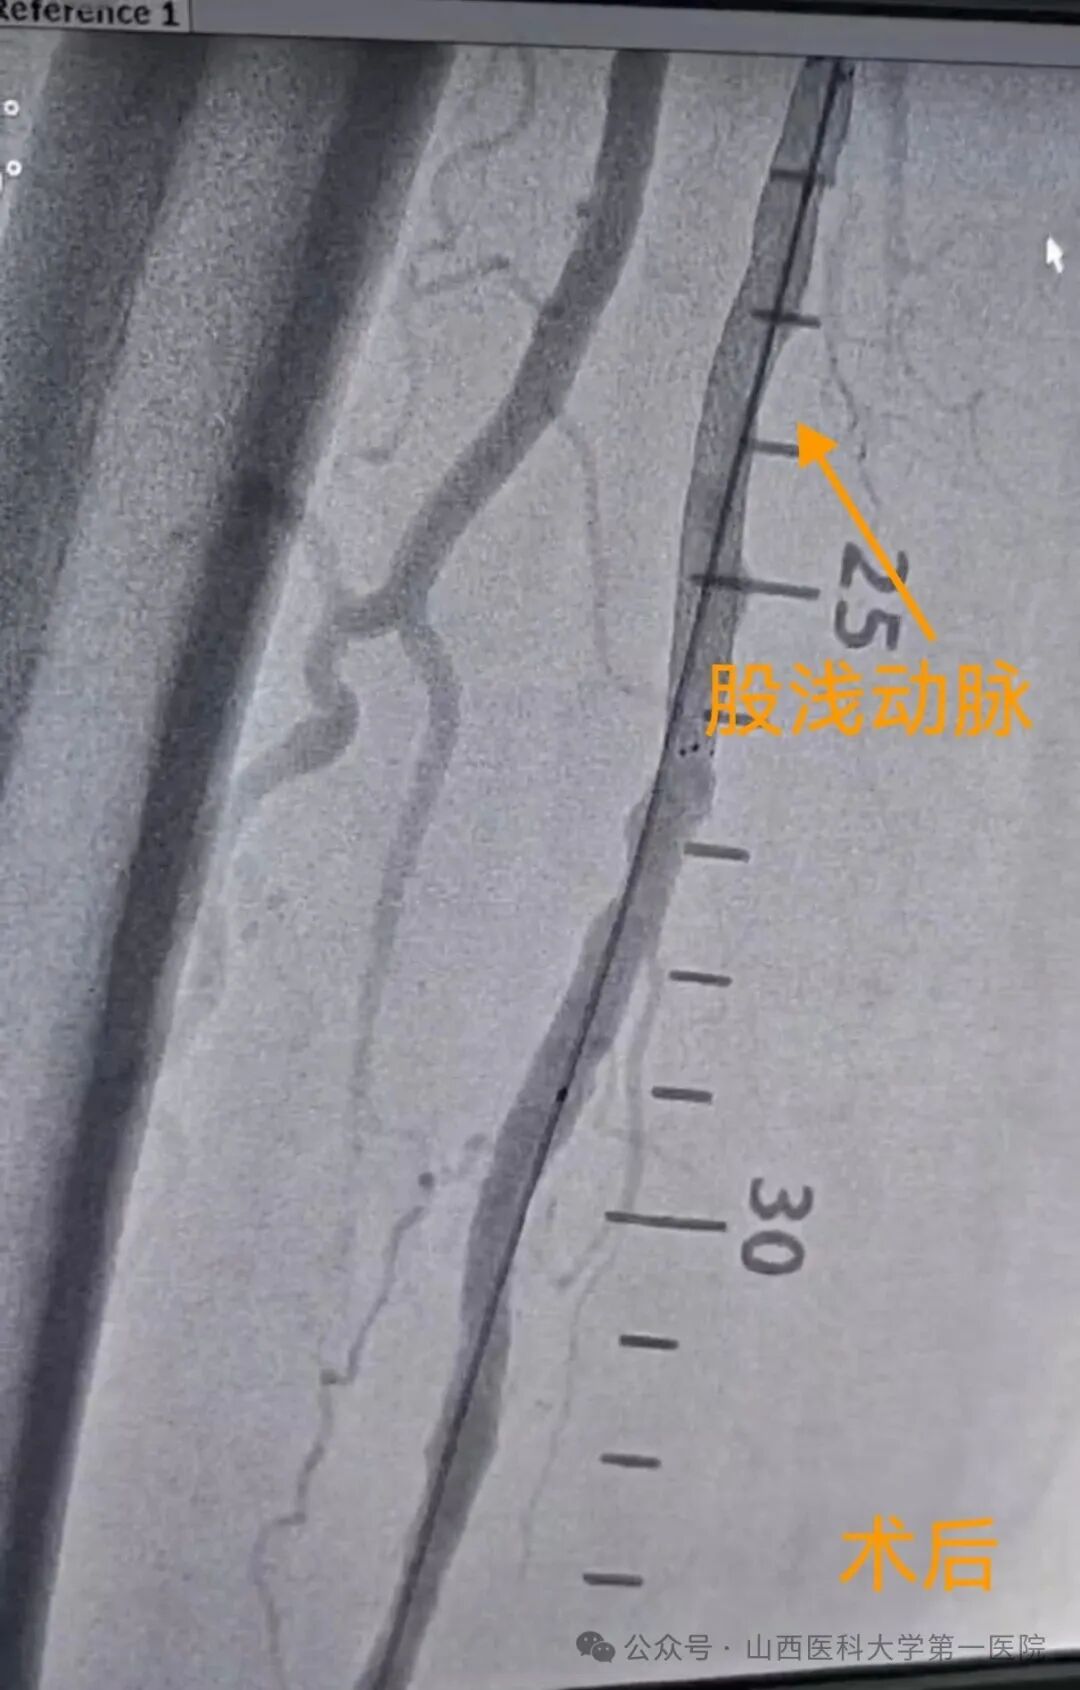

5月29日,在山西医科大学第一医院血管外科手术室内,一场与时间、风险和生命质量的“静默较量”悄然展开,血管外科团队为多种基础疾病缠身的93岁梁奶奶开展了手术风险极高的左股动脉穿刺+右下肢动脉造影+右股浅动脉球囊扩张成形术+支架植入术,打通了闭塞的下肢血管。

“老人的血管像干枯的树枝,脆而易断,我们要在这样的血管里完成导丝通过、球囊扩张和支架植入,每一步都必须稳、准、细。”血管外科主任王贵明说。凭借多年的临床经验和团队协作,他带领手术团队精准操作,成功完成导丝穿通、球囊扩张、支架植入全过程,术中出血不足30ml,老人生命体征始终稳定。